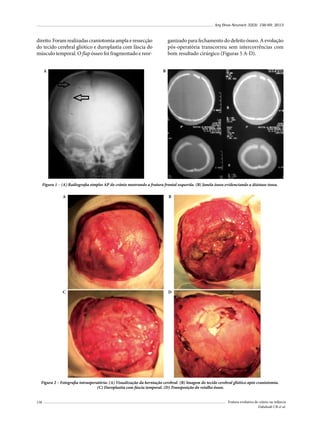

se consideram as fraturas de crânio na infância.25

Muhonen et al.,19 de 1980 a 1993, observaram entre

1.791 fraturas de crânio 10 pacientes com FEC; 9/10 das

crianças eram menores de 1 ano de idade no momento

do TCE. Liu et al.,26 em um período de 20 anos, apresentaram 27 casos de FEC, correspondendo a 0,37% de

todas as fraturas cranianas. Todos os casos nessa série

sofreram TCE, observando-se quedas em 81,5% (22/27)

dos casos, acidentes de trânsito em 18,5% (5/27), e, do